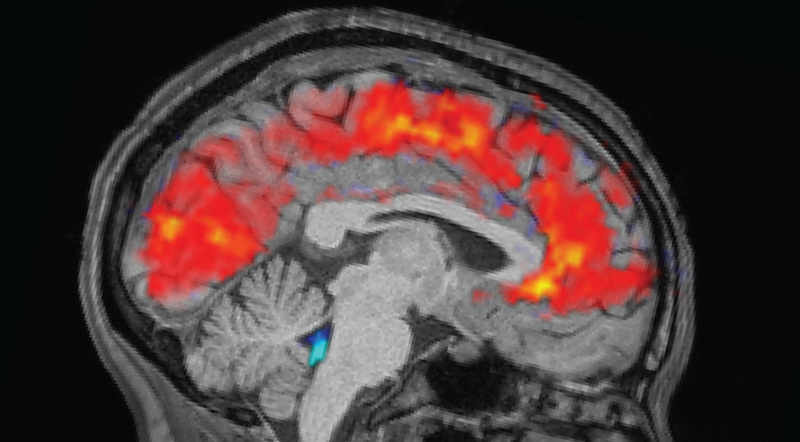

When you zone out after pulling an all-nighter, the brain flushes out cerebrospinal fluid (CSF), which surrounds the brain and spinal cord and is part of the brain's waste-disposal system. This CSF then floods back into the brain when you snap out of it, according to the study, published Oct. 29 in the journal Nature Neuroscience. These fatigue-induced attention failures are also accompanied by massive changes in blood flow and pupil size, the study found. Until now, these physiological responses were not known to work in tandem when the brain spaced out from exhaustion.